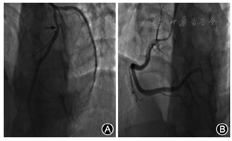

患者男,41岁,因阵发性胸闷、胸痛4个月,晕厥6 h于2018年3月28日入青岛大学附属烟台毓璜顶医院。于4个月前清晨无明显诱因出现发作性胸闷、胸痛,手掌范围大小,疼痛剧烈,伴有濒死感,同时向左上肢放射,每次持续约5 min,含化救心丸可缓解。曾于2017年12月6日就诊我院行心电图示前壁导联T波深倒置改变;心梗三项示:hs-CnI 3 859 pg/ml,CK-MB 7.26 ng/ml;心脏彩超示:EF 68%,室壁节段性运动异常;冠脉造影检查示前降支30%~40%狭窄,左回旋支及右冠脉未见明显狭窄(图1)。住院期间给予抗血小板聚集、抗凝、调脂、缓解冠脉痉挛等药物治疗,但上述症状夜间和凌晨仍偶有发作,将地尔硫卓调量改为30 mg,每8小时一次口服,症状未再出现。出院诊断为"冠心病、急性心肌梗死(继发性)"。患者出院1个月后自行停药。于凌晨4时睡眠中被家属发现意识丧失,给予胸外按压,2~3 min后出现烦躁不安,伴双眼凝视、牙关紧闭、四肢强直及大便失禁,无肢体活动不灵,持续4~5 min后自行缓解。当地医院行颅脑CT检查未见异常。否认心、脑血管疾病病史及其危险因素。